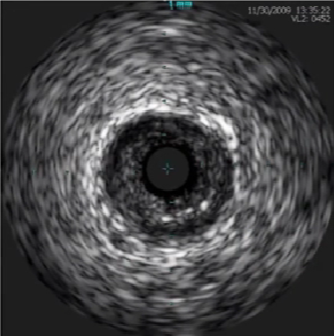

支架贴壁不良

≥1个以上支架柱与管壁之间存在间隙,支架后方有血流回声。

灰阶超声

彩色血流